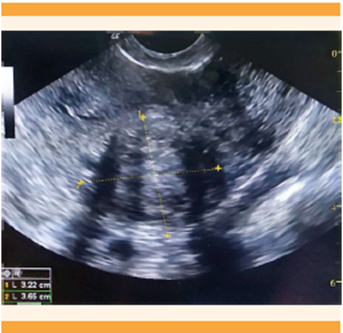

En mujeres posmenopáusicas el grosor endometrial ha demostrado ser un indicador de riesgo de hiperplasia atípica y carcinoma endometrial (Figura 10). Se debe sospechar malignidad, principalmente, en mujeres posmenopáusicas con síntomas y grosor endometrial mayor o igual a 5 mm. 39 Para las pacientes asintomáticas, el punto de corte previamente definido, según el trabajo de Smith R y colaboradores, era de 11 mm; 40 sin embargo, recientemente se propuso un grosor diferente. Se encuentran umbrales muy bajos, como ≥ 5 mm, que han demostrado muy buena sensibilidad, aunque implican costos financieros significativos y una carga emocional debida al seguimiento de una posible malignidad. Con umbrales muy altos (≥ 14 mm) pueden llegarse a perder hasta el 72% de los casos. 41 La evidencia actual demuestra como óptimo un umbral de grosor endometrial ≥ 8 mm, debido a su buen rendimiento para detectar carcinoma endometrial e hiperplasia atípica en pacientes posmenopáusicas asintomáticas. 42 Este umbral ha resultado en un equilibrio entre buena sensibilidad y costos no tan elevados al sistema de salud.

Figura 10 Paciente de 64 años con reporte ecográfico de pólipo endometrial, posterior a histeroscopia. Se evidencian los hallazgos que sugieren malignidad; reporte de patología: adenocarcinoma endometrial de tipo endometrioide.